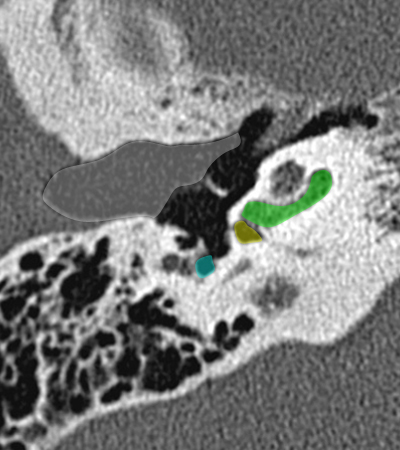

Coupe axiale passant par le canal semi-circulaire supérieur Coupe axiale passant par le canal semi-circulaire latéral Coupe axiale passant par le modiolus de la cochlée Coupe axiale passant par la fenêtre ronde Coupe axiale passant par le ganglion géniculé Coupe axiale passant par l'articulation incudo-malléaire Coupe axiale passant par la partie pétreuse de l'artère carotide interne Coupe axiale passant par le nerf tympanique